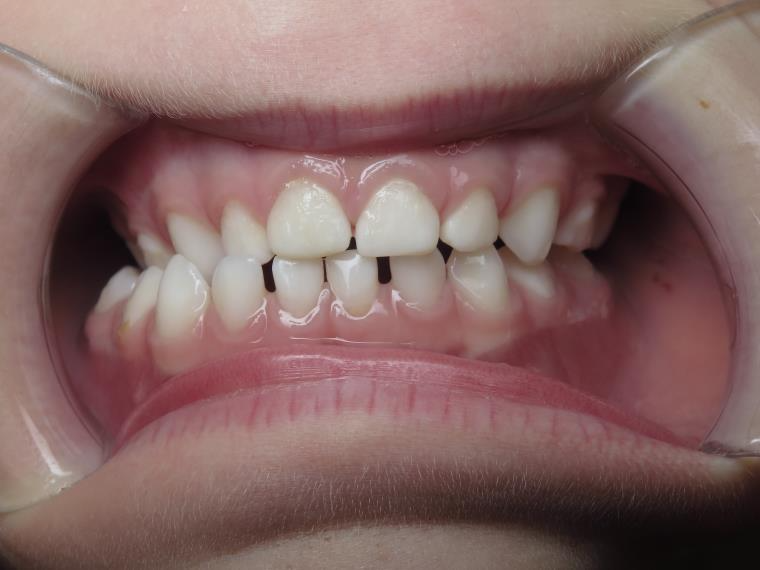

7.inversé droit 4 ans

inversion des dents postérieur coté droit

bilan début et en cours de traitement